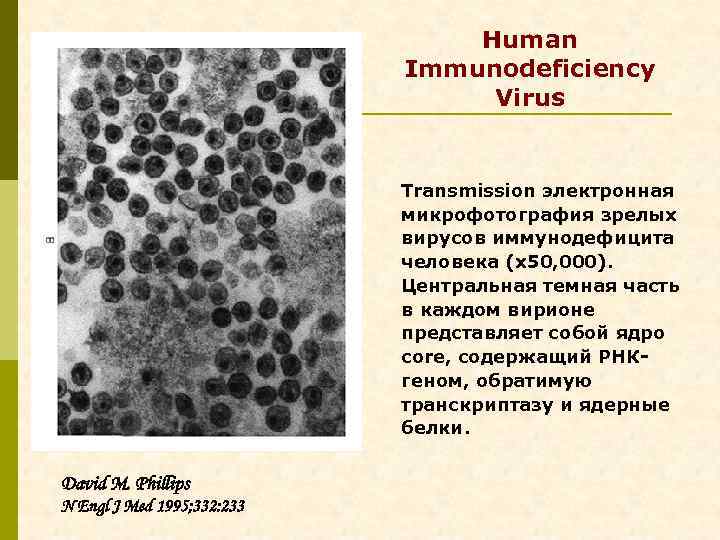

Human Immunodeficiency Virus Transmission электронная микрофотография зрелых вирусов иммунодефицита человека (x 50, 000). Центральная темная часть в каждом вирионе представляет собой ядро core, содержащий РНКгеном, обратимую транскриптазу и ядерные белки. David M. Phillips N Engl J Med 1995; 332: 233